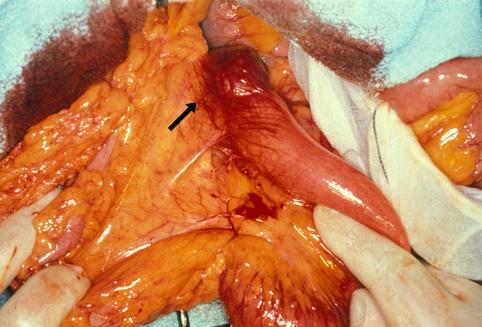

악성 비상피성종양 평활근육종 (소장)

공장 상부의 장막측에 발생한 평활근육종

악성 비상피성종양/평활근육종

소장/공장

종양의 최대경(밀리미터)

40이상